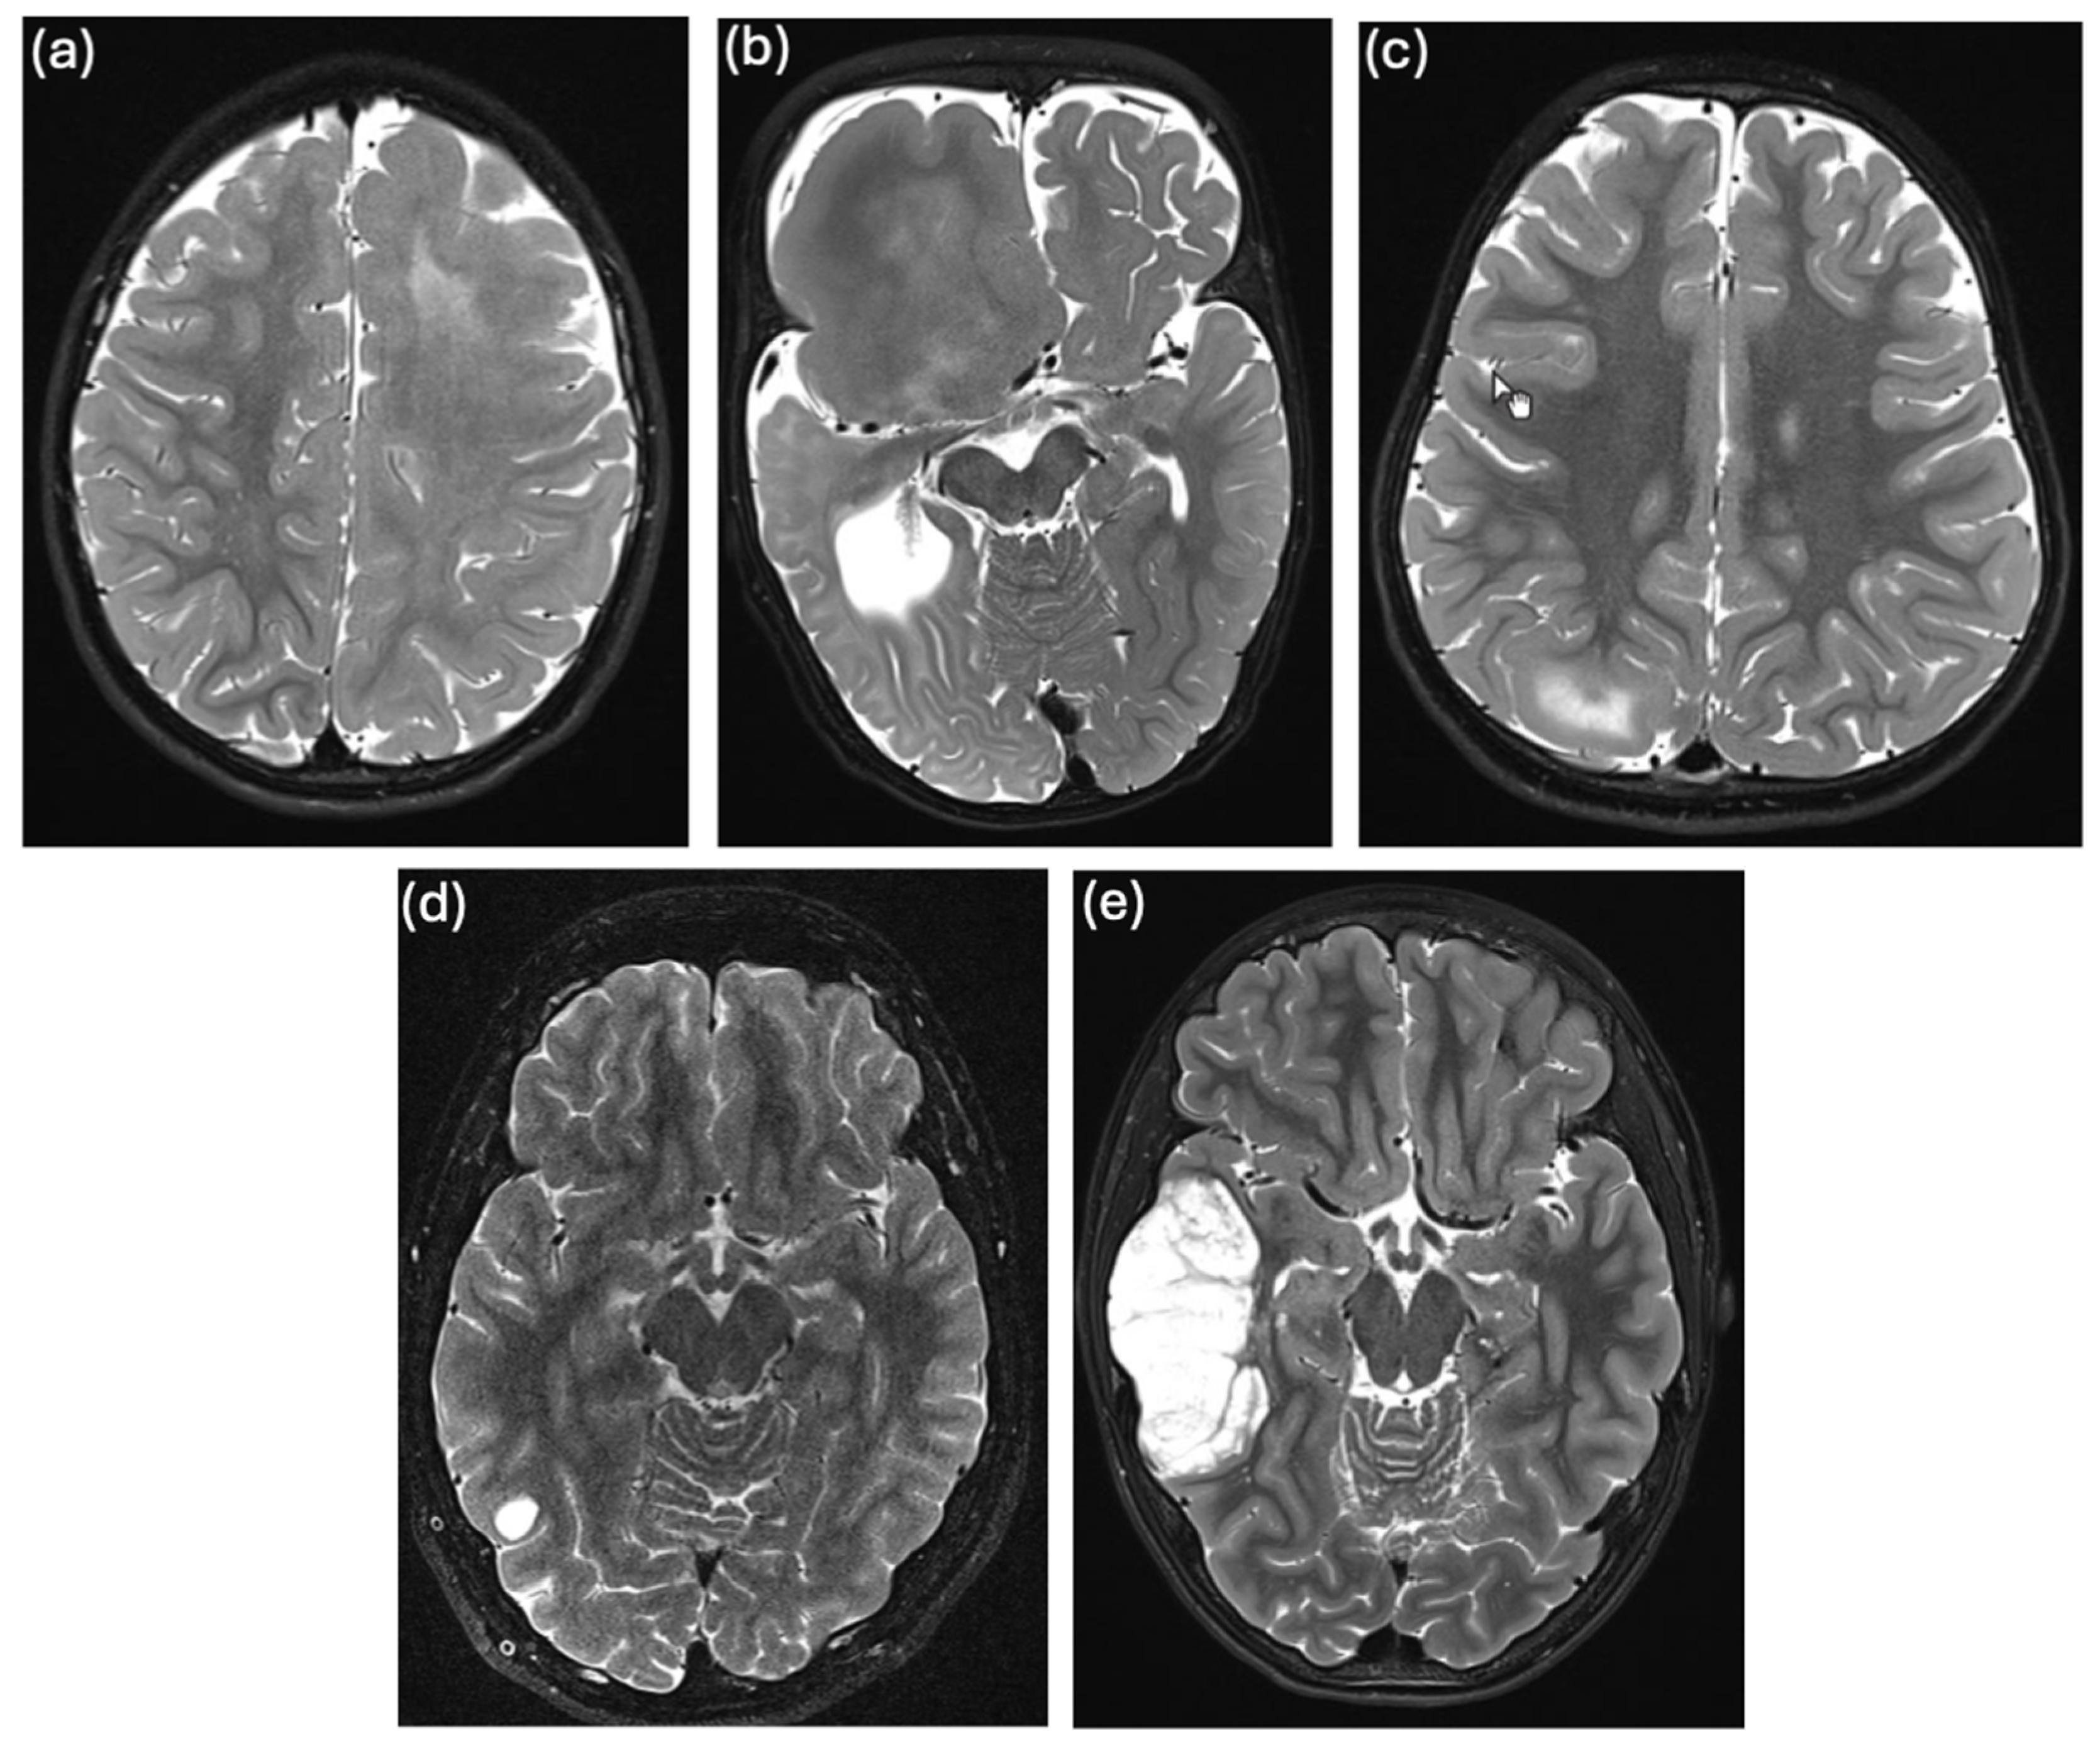

| 3 | B | 2.5 | cMRI: HMEG; histology: reactive gliosis | no | MTOR | 100× | 127 |

| 4 | B | 1.9 | cMRI: focal megalencephaly; histology: reactive changes | Gli3 (NM_000168.6), c.4430_4439del (het), p.S1477fs | PIK3CA | 100× | 145 |

| 5 | B | 3.5 | cMRI: FCD; histology: FCDIIb | ATP1A2 (NM000702.4), c.2827C>T (het), p.Q943* | TSC2 | 100× | 217 |

| 6 | B | 1.9 | cMRI: FCD; histology: FCDIIb | nd | no | 100× | 250 |

| 7 | B | 10.5 | cMRI: PMG, hemiatrophy; no histology | Del2p15 | no | 100× | 181 |

| 8 | B | 0.5 | cMRI: TSC; histology: TSC | TSC2 (NM_000548.5), c.4606C>T (het), p.Q1536* and Del17q12 | no | 100× | 149 |

| 9 | B | 16.9 | cMRI: FCD; histology: FCDIIa | no | no | 100× | 118 |

| 10 | B | 5.3 | cMRI: TSC; histology: TSC | TSC1 (NM_000368.5), c.2257dup (het), p.S753Kfs*8 | no | 500× | 9058 |

| 11 | B | 0.3 | cMRI: FCD; histology: FCDIIb | no | no | 500× | 11,241 |

| 12 | B | 4.5 | cMRI: complex MCD, PMG; histology: connective tissue 1 | no | no | 500× | 10,700 |

| 13 | C | 8.5 | cMRI: FCD, HC atrophy; histology: focal cortical gliosis 2, HS type I 3 | no | no | 100× | 171 |

| 14 | D | 2.5 | cMRI: unilateral cavernous venous malformation; histology: cavernous dilatation of vessels, consistent with venous angioma | no | no | 500× | 6723 |

| 15 | E | 16.7 | cMRI: LGGNT; histology: DNET or RGNT | nd | FGFR1, PIK3R1 | 100× | 120 |

| 16 | E | 13.9 | cMRI: DNET; histology: DNET | nd | FGFR1 | 100× | 340 |

| 17 | E | 9.0 | cMRI: DNET, MVNT or other GNT; histology: LGGNT | nd | no | 100× | 158 |

| 18 | E | 9.2 | cMRI: glial tumor; histology: glial tumor | no | no | 500× | 21,988 |

| 19 | F | 14.7 | cMRI: partial MCA infarction; histology: acute hypoxic-ischemic infarction | no | no | 100× | 120 |

| 20 | F | 15.0 | cMRI: ICA occlusion; no histology | no | no | 100× | 176 |